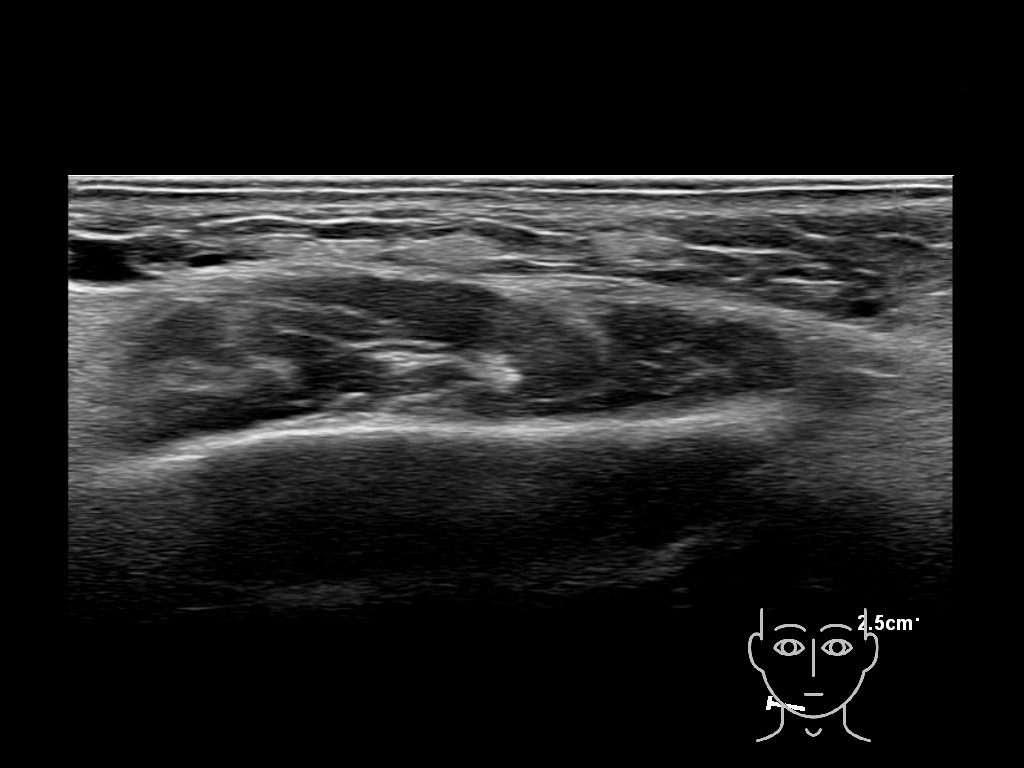

Fillers

Draw in the image on the right where the fillers are located. To check if your answer is correct, please click on the secondary image.

Fillers

Draw in the second image below where the fillers are located. To check if your answer is correct, swipe the first image to the right.